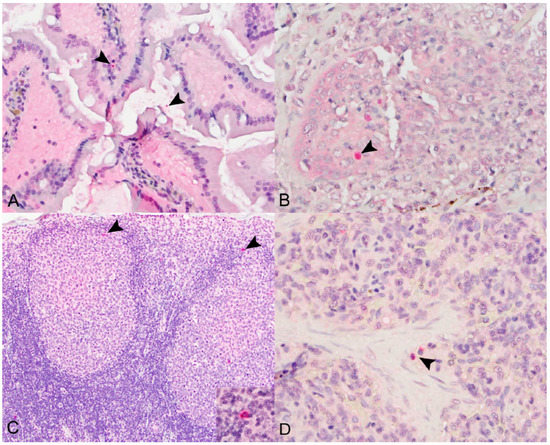

3.1. Histopathology

3.1.1. Small Intestines

3.1.2. Salivary Glands

3.2. Immunohistochemistry

3.2.1. SOSV Tissue Tropism